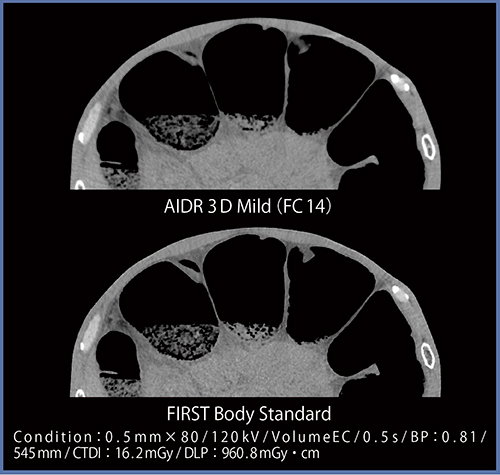

●症例8:交通外傷

本症例は上肢挙上困難であり,CTにて肘の付近に強いストリークアーチファクトが発生した。胸水が貯留しているものの,AIDR 3Dでは血性胸水かどうかの判断は困難であるが,FIRSTではアーチファクトがかなり低減し,胸水の濃度が評価しやすくなっている(図10)。

図10 症例8:交通外傷